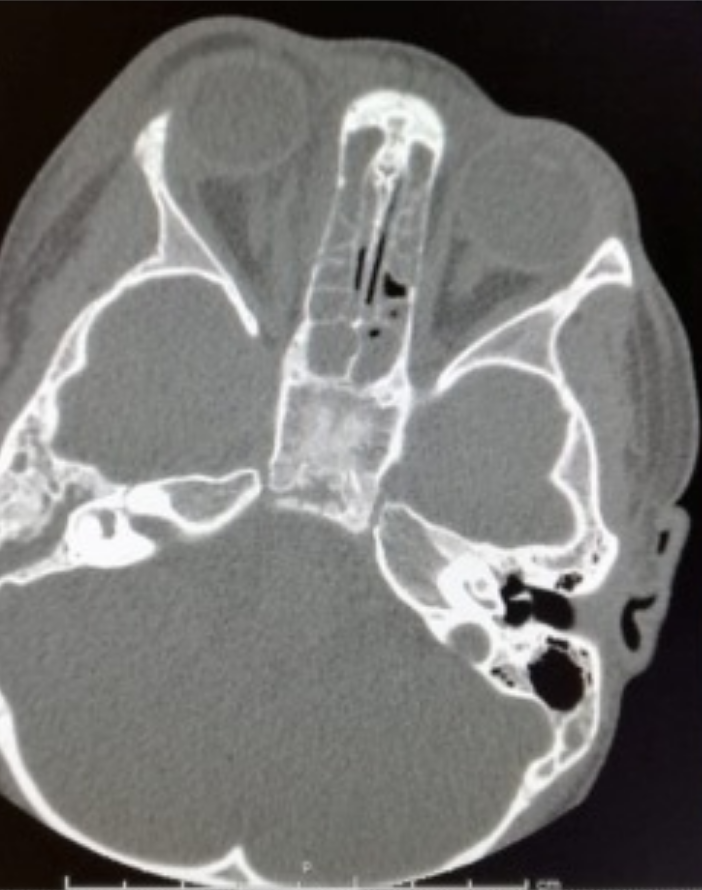

Torretta S, Guastella C, Marchisio P, et al. Sinonasal-Related Orbital Infections in Children: A Clinical and Therapeutic Overview. J Clin Med. 2019;8(1):101. Published 2019 Jan 16. doi:10.3390/jcm8010101 (cropped)

• Orbital CT with contrast to rule out orbital disease

Torretta S, Guastella C, Marchisio P, et al. Sinonasal-Related Orbital Infections in Children: A Clinical and Therapeutic Overview. J Clin Med. 2019;8(1):101. Published 2019 Jan 16. doi:10.3390/jcm8010101

• Orbital cellulitis, OD